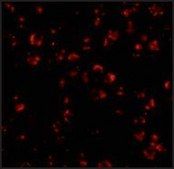

immunocytochemistry: suitable